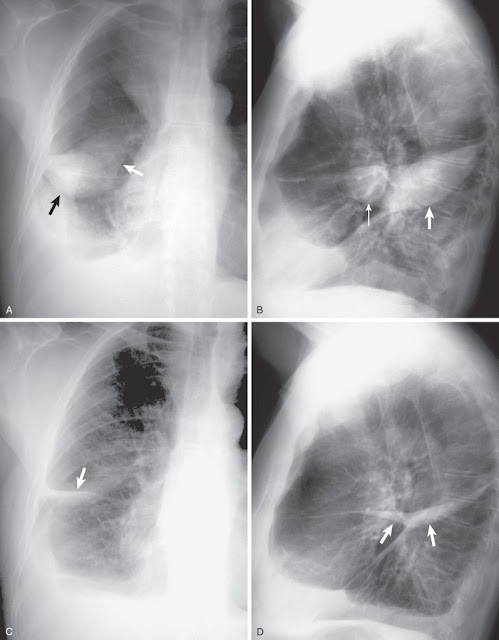

Hình 2. Hình ảnh giả u phổi. (A) X quang thẳng tư thế sau-trước bệnh nhân suy tim trái cho thấy dịch ở rãnh liên thùy nhỏ (mũi tên đen) và lớn (mũi tên trắng) giống một khối u. Ngoài ra có dịch tự do khoang màng phổi phải cho hình ảnh tù góc sườn hoành. (B) X quang chụp nghiêng cho thấy mờ khu trú rãnh liên thùy nhỏ (mũi tên mảnh) và lớn (mũi tên dày). (C) Xquang thẳng chụp sau 1 tuần cho thấy giảm lượng dịch giữa các thùy. (D) Xquang nghiên tương ứng cũng cho thấy giảm lượng dịch sau khi chức năng tim đã cải thiện.